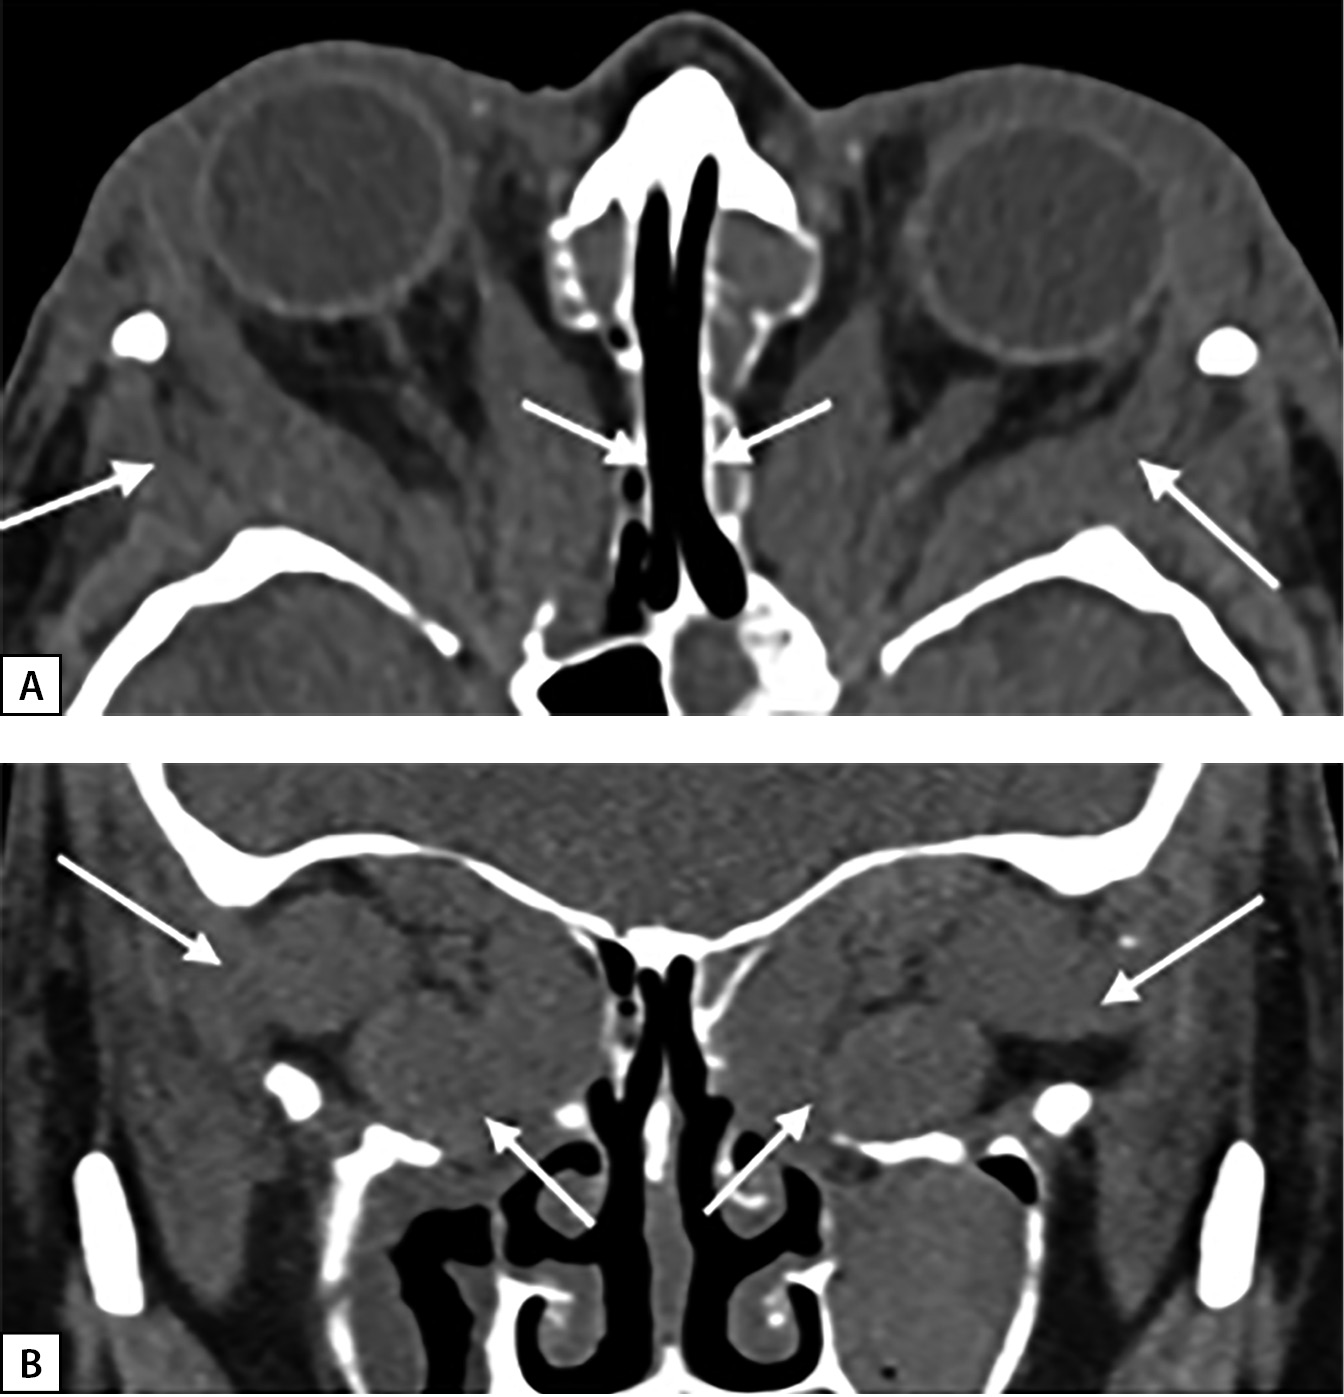

В связи с резистентностью к лечению ГК и двусторонней оптической нейропатией в ФГБНУ «НИИ глазных болезней» в октябре и ноябре 2018 г. были выполнены последовательно глубокая латеральная и медиальная (эндоназальная трансэтмоидальная) декомпрессия левой и правой орбиты. После операций достигнута четкая положительная динамика по зрительным функциям: повышение остроты зрения с 0,7 до 1,0; данным компьютерной периметрии и параметрам цветового зрения. В наиболее тяжелых случаях оптической нейропатии при больших мышцах эффективен максимальный объем декомпрессии — 2,5 стенок [12]. На МСКТ после операций на орбитах отмечается адекватное увеличение объема костной орбиты в задней части, необходимое при апикальном синдроме (рис. 2, А, В). В дальнейшем, последовательно до апреля 2019 г., выполнены: коррекция вертикально-горизонтального косоглазия и коррекция ретракции век с хорошим эффектом.

Рисунок 2. МСКТ орбит через 1 месяц

после глубокой латеральной и медиальной декомпрессии:

А — смещение увеличенных прямых мышц

в сформированные костные окна

(аксиальная проекция), белые стрелки;

В — экспансия мягкотканных структур,

прежде всего мышц за пределы резецированных наружной,

медиальной и внутренней части нижней стенки орбиты

(корональная проекция), белые стрелки.